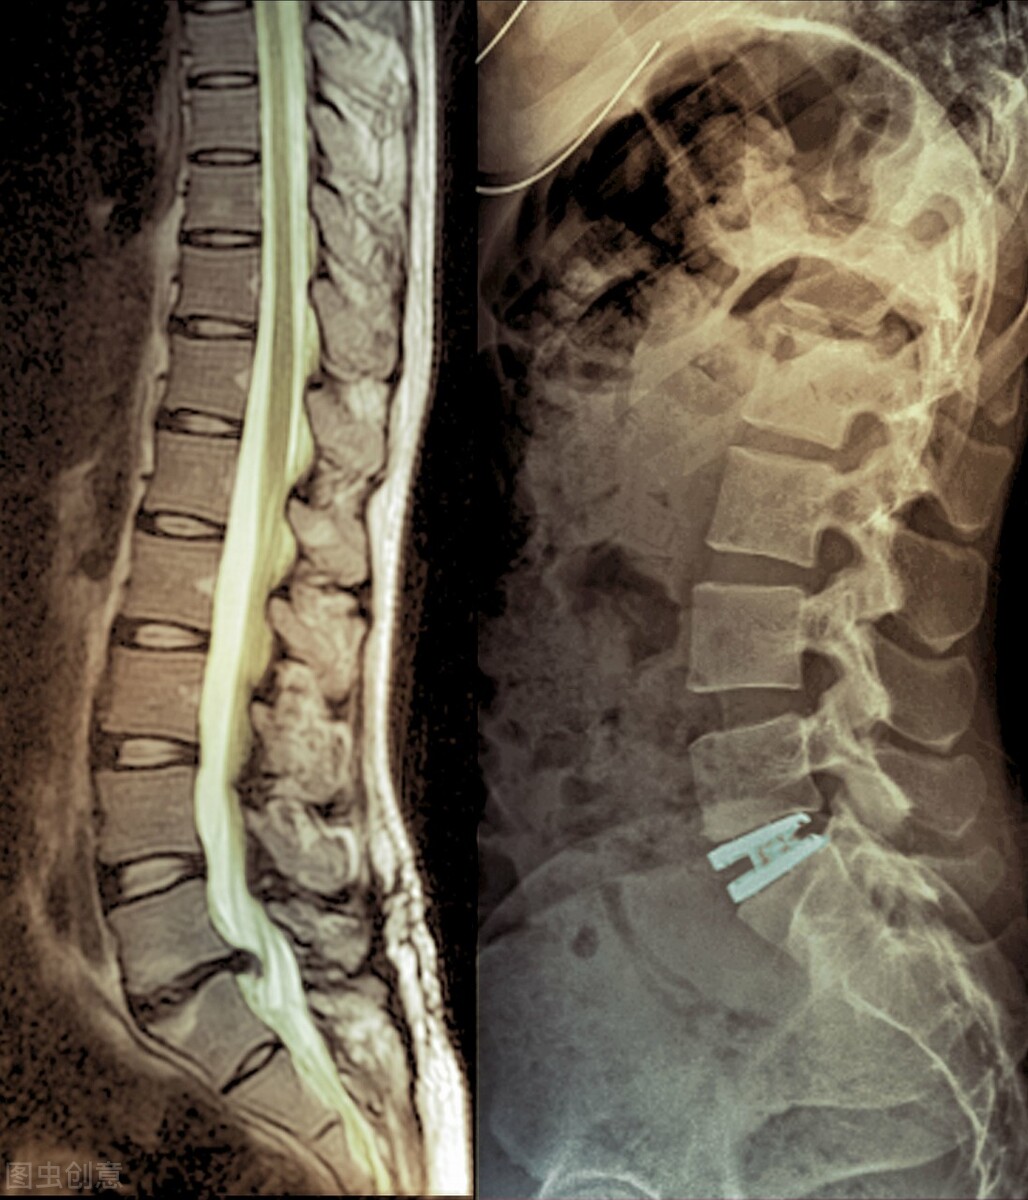

老熊有多年的腰痛,进行拍片检查发现是腰椎间盘的缘故,突出有点严重,但是担心手术的风险,所以还是坚持进行保守治疗,希望通过相对安全的方法进行治疗,毕竟已经一大把年纪了,再去手术觉得自己的身体已经吃不消了。

治疗了大概三个月左右,整体的效果还是非常满意的,之前腰背部根本直不起来,现在能自己起来,原先腿脚麻木不适,现在麻木的情况也好转不好,可是有一个问题,就是不能长距离走路,走路太多就会出现腰背部的下沉感,好像腰部没有了支撑,腰背部有一种空落落的感觉,之前还怀疑是椎管狭窄引起的间歇性跛行,但是拍片显示狭窄不是很严重,但是这个腰部的问题一直得不到很好解决。